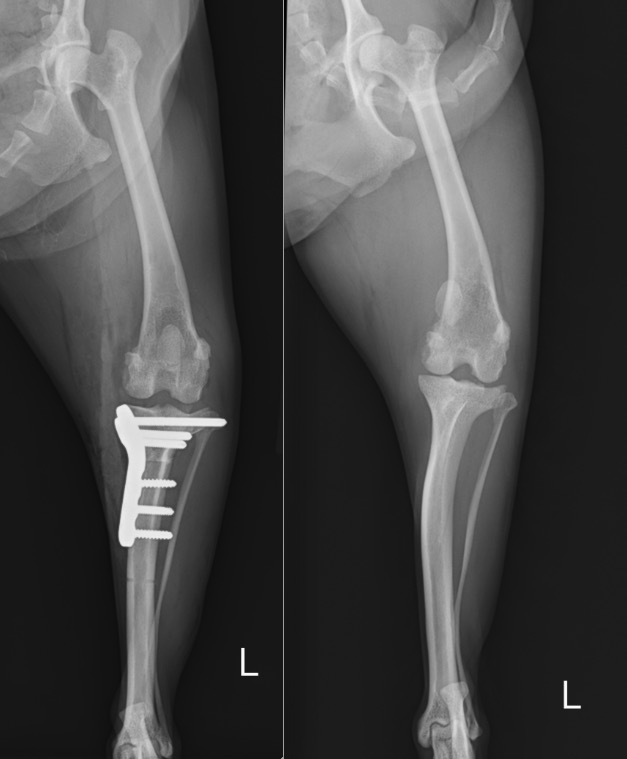

本症例は膝蓋骨内方脱臼に対する手術を行い脱臼を整復すると同時に、前十字靭帯損傷による膝の不安定性に対しTPLO(Tibial Plateau Leveling Osteotomy:脛骨高平部水平化骨切術)を実施しました。

手術前と手術後のX線写真を比べると、膝のズレが解消し、お皿の骨も真ん中に整復されていることが分かるかと思います。

左:術後 / 右:術前